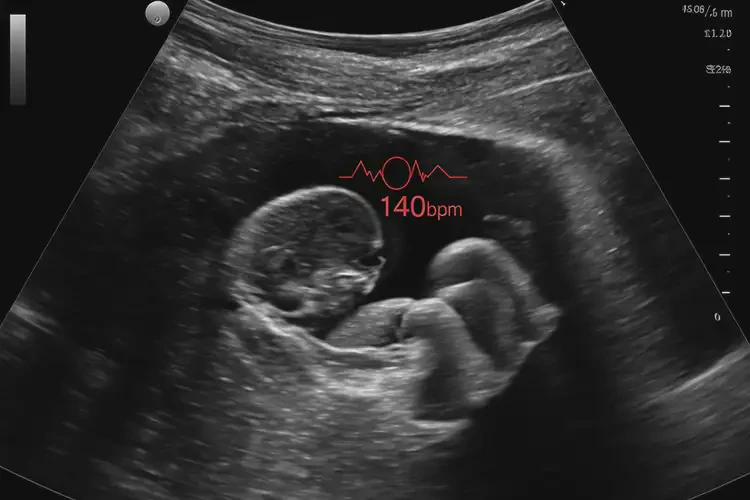

懷孕第29周胎心183還能保住嗎(圖1)

懷孕第29周胎心183還能保住嗎(圖2)

懷孕第29周胎心183還能保住嗎(圖3)

懷孕第29周胎心183還能保住嗎(圖4)